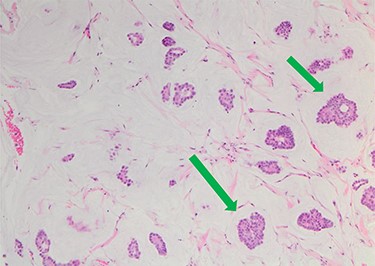

She underwent triple assessment. Bilateral mammogram showed no abnormality in either breast. However, right axillary accessory breast tissue had notably increased in size since her previous mammogram (7 months earlier) and displayed slight distortion (R3) (Fig. 1). Ultrasound scan of the right axilla showed accessory breast tissue measuring 56 × 50 mm in its maximum dimension without any abnormal axillary lymph nodes. Furthermore, the palpable lump showed indeterminate characteristics (U3) measuring 10.9 × 8.3 mm (Fig. 2). Ultrasound-guided core biopsy of the abnormality showed Grade 1 mucinous adenocarcinoma (Fig. 3) which was oestrogen and progesterone receptor positive (Quick score of 8) and Her-2 negative. There was no evidence of lymphoid tissue in the core biopsy.

Nests of tumour cells with intermediate-grade nuclei are seen within pools of extra-cellular mucin 10× haematoxylin and eosin stain (green arrow).